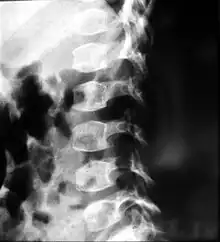

| A: A 6 year-old male with spondyloepiphyseal dysplasia congenita. Short stature, disproportionately short trunk, and kyphoscoliosis. B: Preoperative and postoperative X-ray | |

People with spondyloepiphyseal dysplasia are short-statured from birth, with a very short trunk and neck and shortened limbs. Their hands and feet, however, are usually average-sized. This type of dwarfism is characterized by a normal spinal column length relative to the femur bone. Adult height ranges from 0.9 meters (35 inches) to just over 1.4 meters (55 inches). Curvature of the spine (such as kyphoscoliosis and lordosis) progresses during childhood and can cause problems with breathing. Changes in the spinal bones (vertebrae) in the neck may also increase the risk of spinal cord damage. Other skeletal signs include flattened vertebrae (platyspondyly), a hip joint deformity in which the upper leg bones turn inward (coxa vara), and an inward- and downward-turning foot (called clubfoot). Decreased joint mobility and arthritis often develop early in life. Medical texts often state a mild and variable change to facial features, including cheekbones close to the nose appearing flattened, although this appears to be unfounded. Some infants are born with an opening in the roof of the mouth, which is called a cleft palate. Severe nearsightedness (high myopia) is sometimes present, as are other eye problems that can affect vision such as detached retinas. About one-quarter of people with this condition have mild to moderate hearing loss.[2]

- X-ray